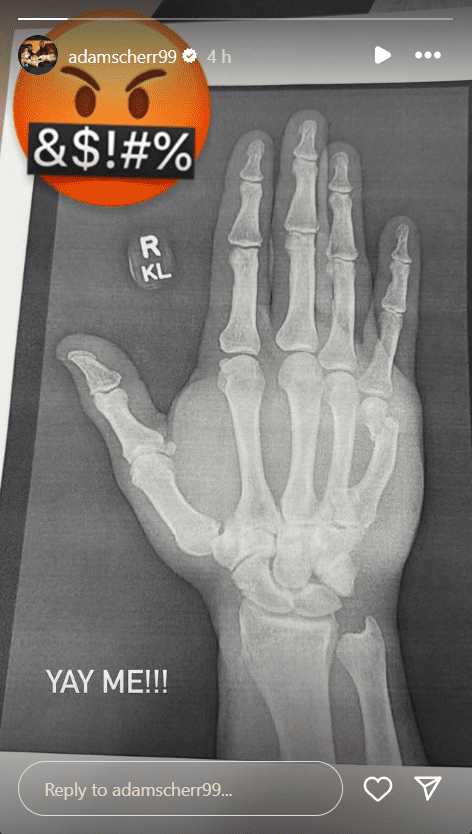

The Monster Among Monsters took to his Instagram story and uploaded a photo of an X-ray, revealing that he suffered a broken wrist injury. He included an angry emoji that was cursing and added a sarcastic comment, saying, “YAY ME!!”